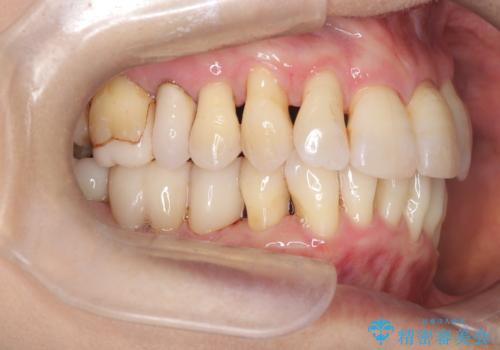

- 歯周病で歯茎が下がり根っこの部分が見えている状態で3か月のメンテナンスをコンスタントに通われている方です。

ブラッシングは歯間ブラシや部分歯ブラシなどの補助道具も使用し時間をかけて丁寧に磨いていらっしゃるのですが、ブラッシング圧に気を付けながらの為バイオフィルムが根っこの部分に残っているのです。

いつも時間をかけて丁寧に磨いていらっしゃるようですが染め出しをしてみると歯茎が下がっている部位はバイオフィルムの付着が見られました。